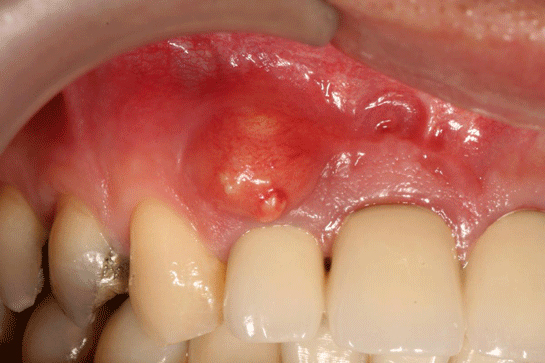

Diş iltihabı, dişlerin etrafındaki dokuların iltihaplanması durumunu ifade eder ve genellikle diş eti iltihabı (gingivitis) veya diş kökü iltihabı (apikal periodontitis) olarak sınıflandırılır. Diş iltihabının belirtileri ve tedavi yöntemleri, hastalığın evresine ve türüne göre değişiklik gösterir. Bu makalede diş iltihabının belirtileri, nedenleri ve tedavi yöntemleri üzerinde durulacaktır. Diş İltihabının Belirtileri Diş iltihabının belirtileri, genellikle aşağıdaki gibi sıralanabilir: